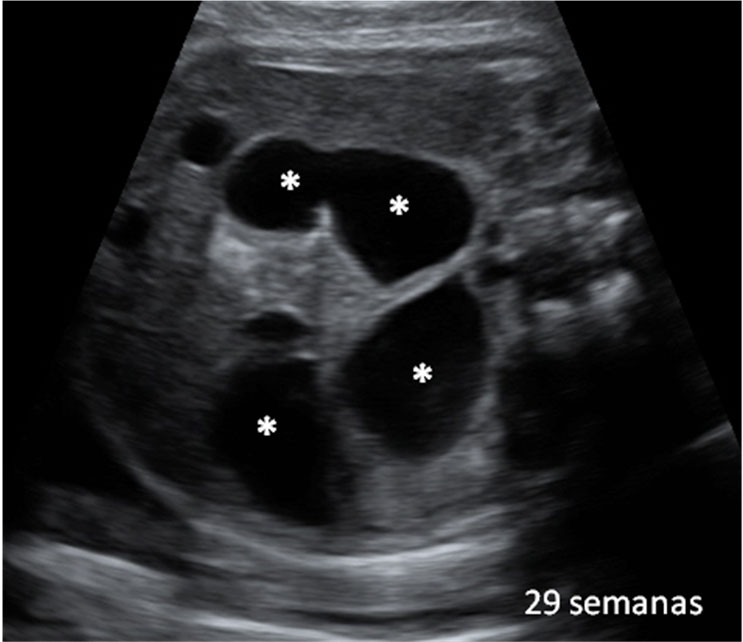

Esta ecografía 4D de la semana 20 de embarazo muestra que los bebés prácticamente empiezan a chuparse el dedo dentro del útero materno. El feto se acerca el dedo pulgar a la boca y en las imágenes finales la abre, muy probablemente para chupárselo.

Perfil de un bebé con el dedo pulgar cerca de la boca

En las imágenes del final, se puede apreciar cómo la criatura incluso abre la boca, quizá para chuparse el dedo pulgar. Es un reflejo el de succión que mantendrá fuera del útero, ya sea con su propio dedo o mediante la lactancia materna.